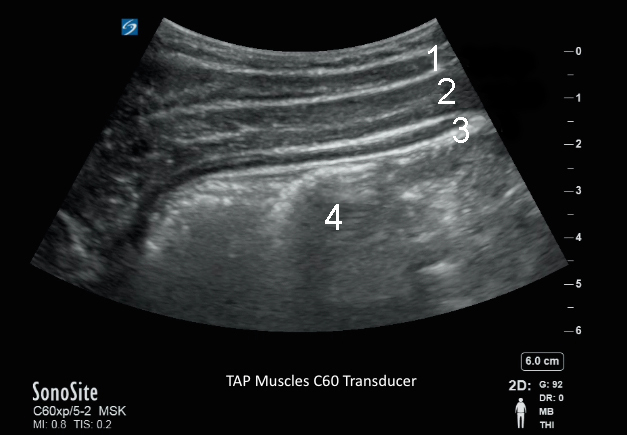

Darstellung der TAP-Muskeln mit Schallsonde C60

1. Musculus obliquus externus

2. Musculus obliquus internus

3. Muskel, transversal

4. Peritonealhöhle